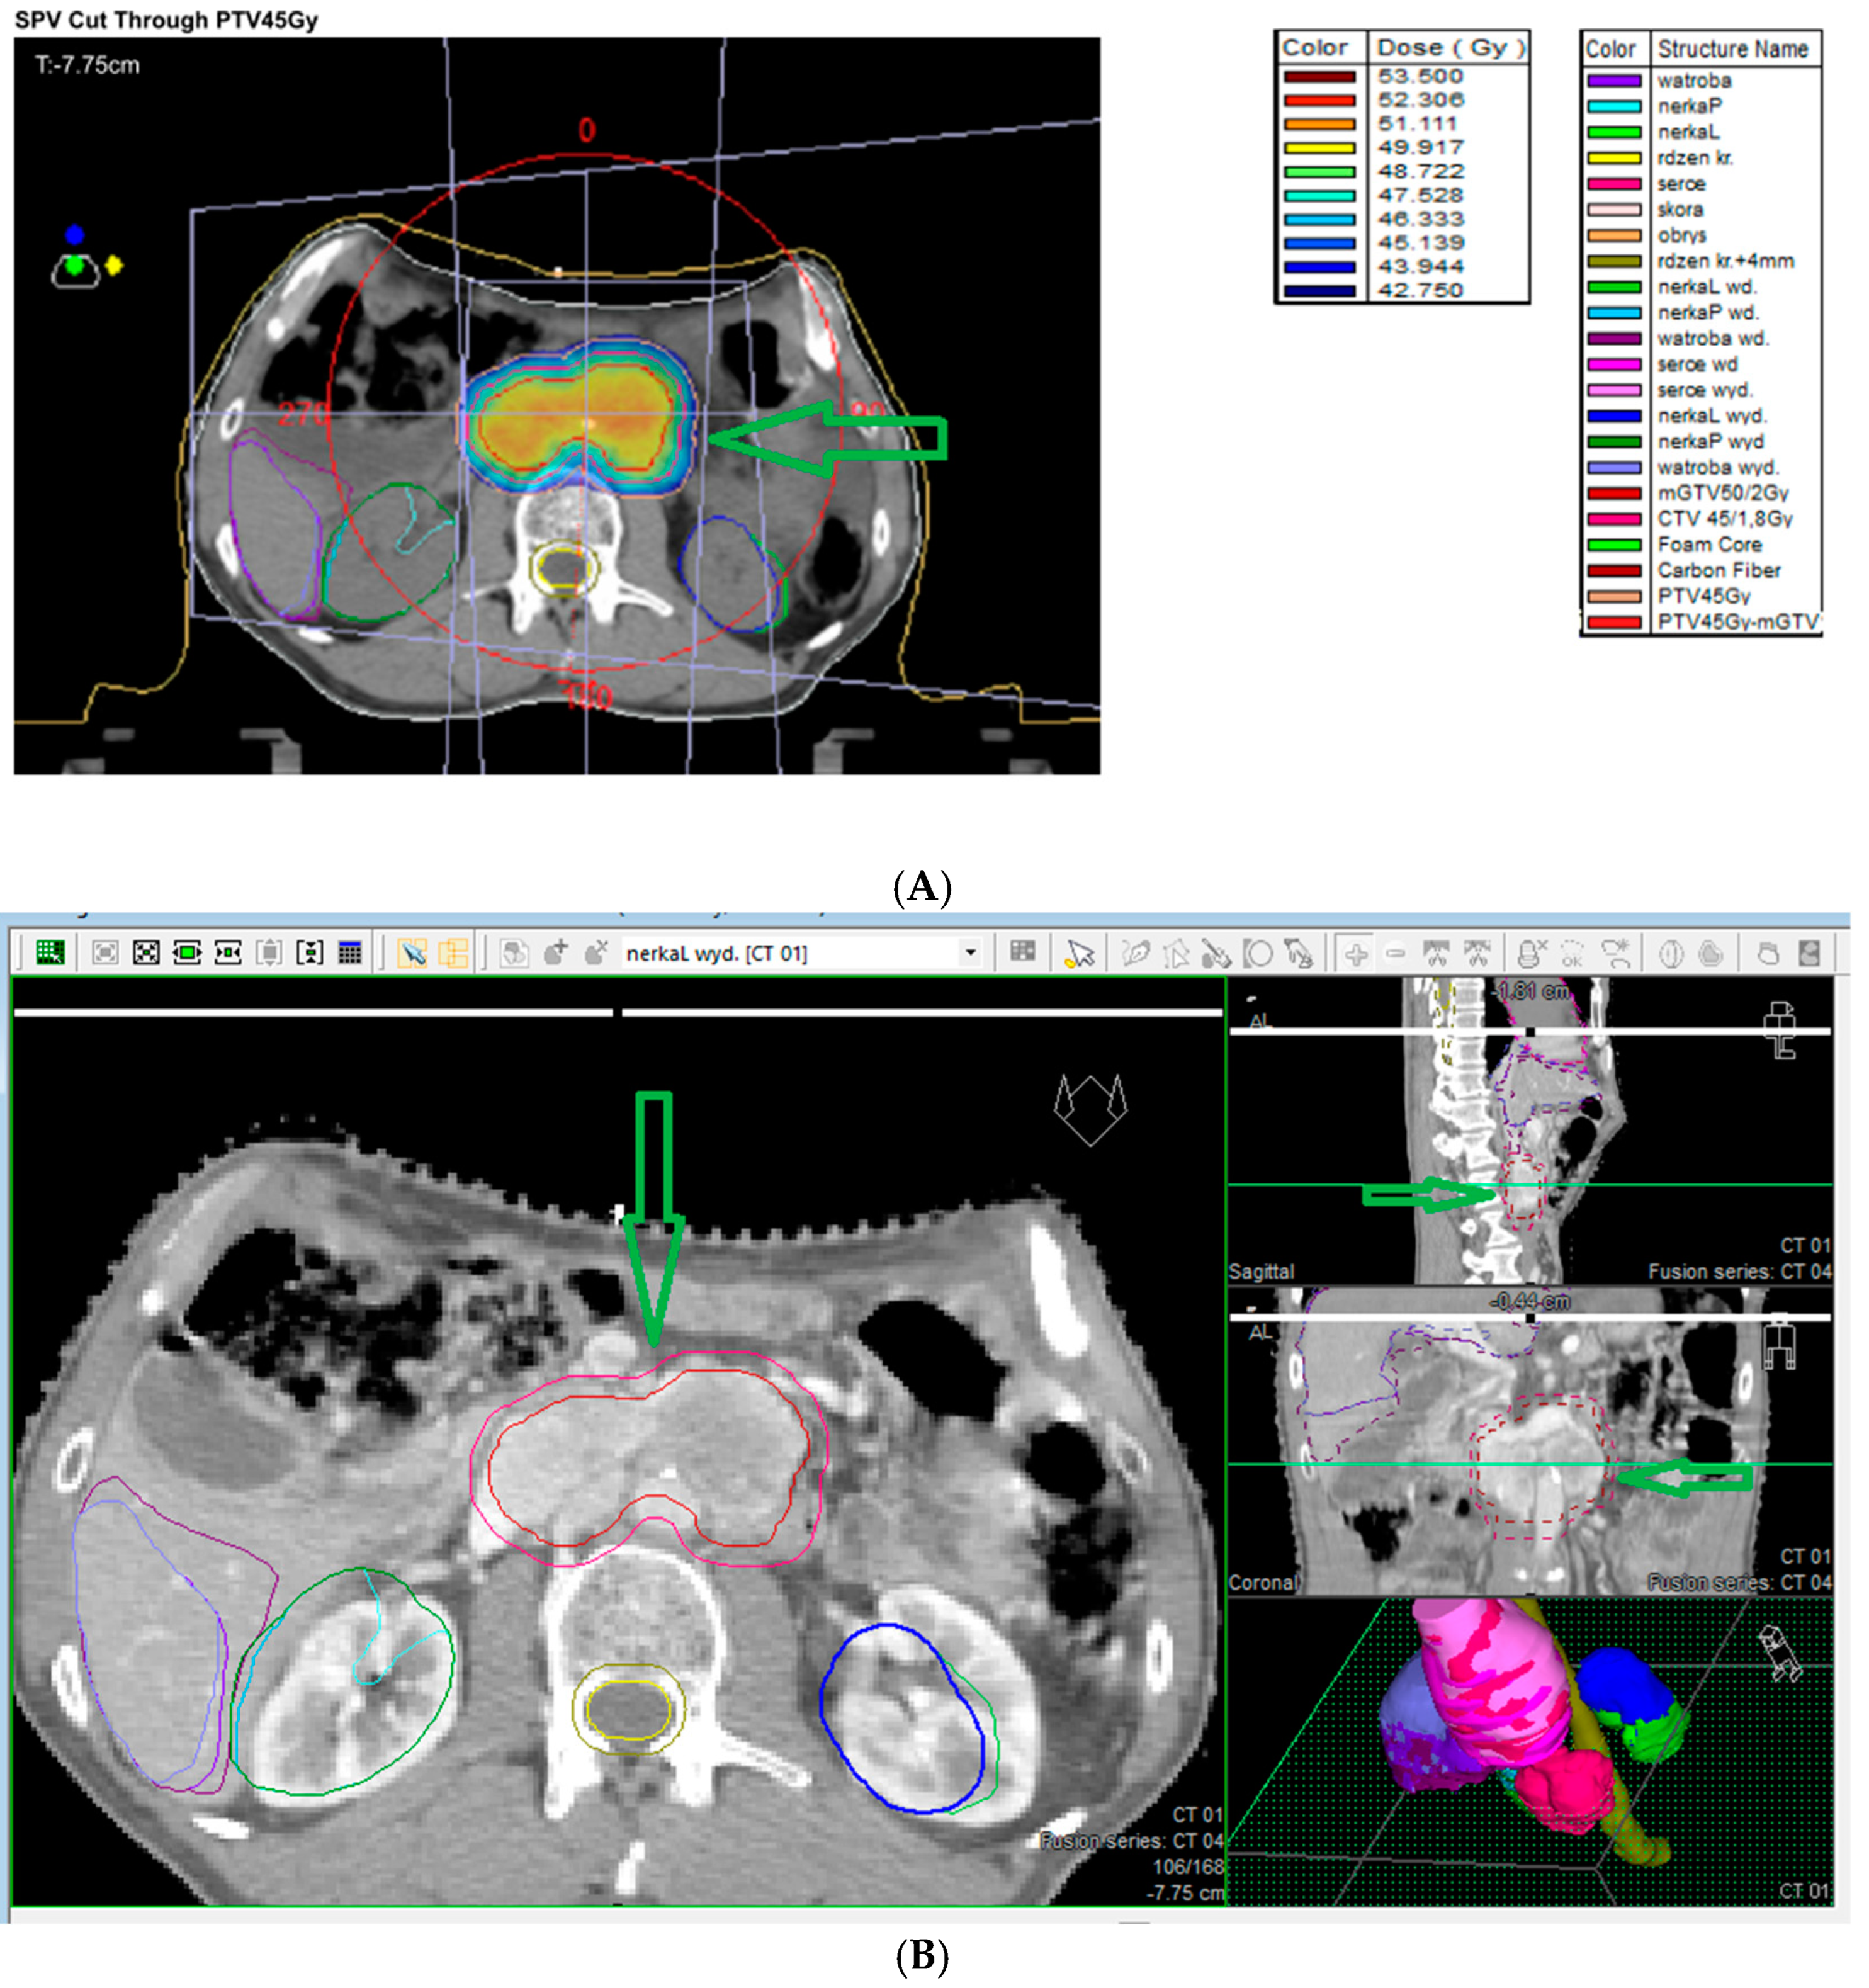

7.9. External Beam Radiotherapy (ERBT) and Hypofractionated Stereotactic Radiotherapy (hSRT)